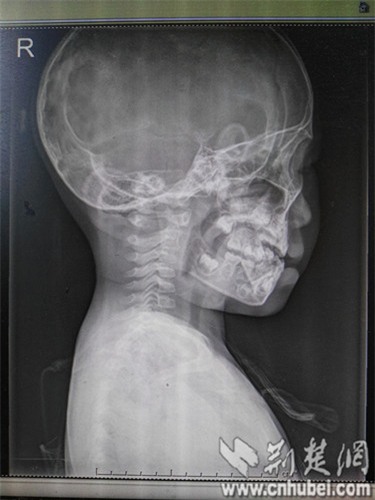

Trước đó, vào tối ngày 11/6/2016, bé gái Phương Phương (3 tuổi) tự nhiên bị sốt cao 38,5 ℃. Sang ngày thứ hai thì bố mẹ thấy em có hiện tượng bị vẹo cổ sang bên trái và cứ thế giữ yên không quay được.

Tình hình có vẻ trầm trọng hơn khi bé bắt đầu quấy khóc, bố mẹ bé đã phải đưa đến bệnh viện Phổ Nhân (Trung Quốc) để khám nghiệm.

Sau khi bác sĩ nhi khoa thăm khám và chẩn đoán là viêm amiđan mủ cấp tính, do cổ của bé có hiện tượng bị hạn chế vận động.

Theo bác sĩ Hồ Tiểu Quân, giám đốc bệnh viện Phổ Nhân, người trực tiếp xem xét bệnh tình của Phương Phương cho biết, bé còn rơi vào hiện tượng căng cơ bắp vùng cổ, xuất hiện đau rõ ràng.

Đây là hiện tượng thoái hóa đốt sống cổ, tổn thương nặng vùng cơ trên phần cổ, cần phải lập tức điều trị phục hồi chức năng, trị liệu nhanh để hồi phục công năng hoạt động của cổ.